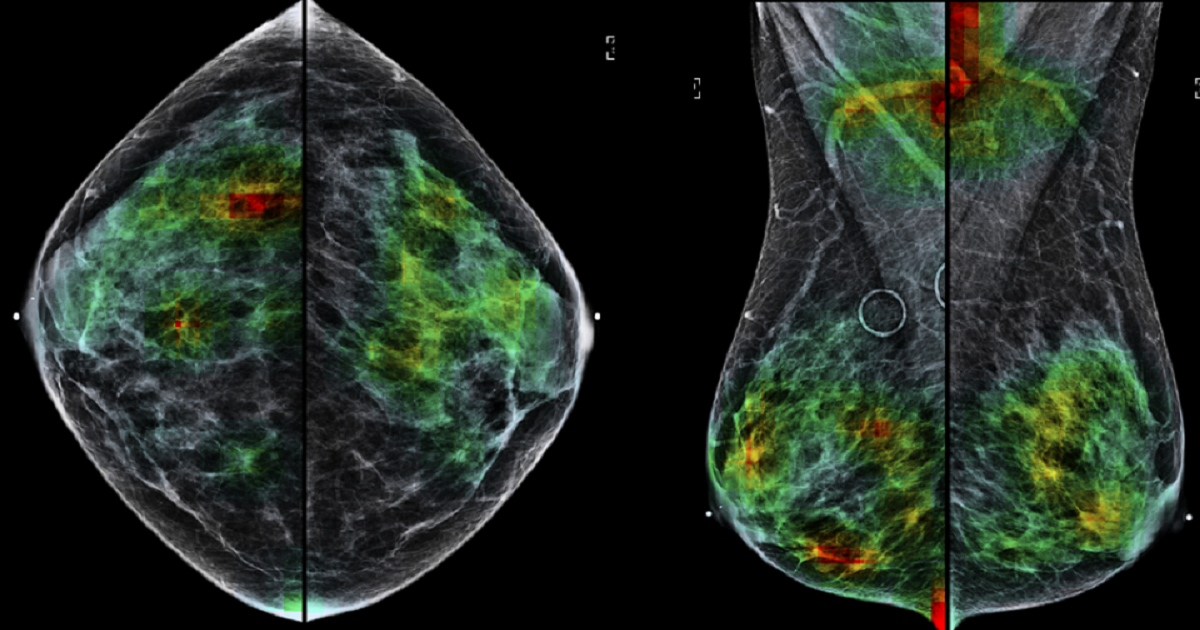

One of the most prominent applications is in radiology, where computer vision has demonstrated its ability to detect disease with remarkable accuracy by examining X-rays, CT scans and MRIs. Image processing assists pathologists in analyzing tissue samples, dermatologists in diagnosing skin cancer, and ophthalmologists in fundus examinations and retinal scans. Beyond diagnosis, computer vision contributes to the remote monitoring of patients. The ethical dimensions and regulatory frameworks surrounding these technologies are evolving in parallel with their rapid integration into healthcare systems.